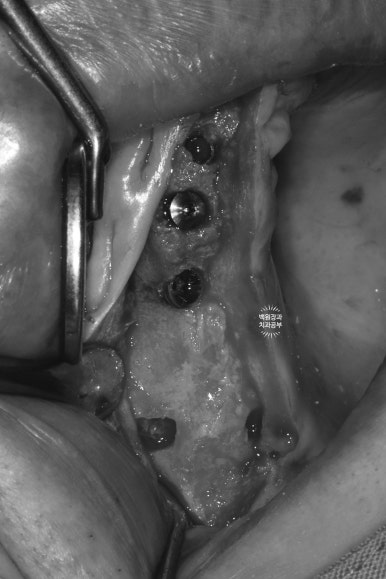

잇몸뼈가 너무 얇다보니, 임플란트를 위치시키면 이렇게 임플란트의 일부가 드러날 수 밖에 없었고, 이제 어렵디 어려운 잇몸뼈이식이 기다리고 있는 상황..

저희 병원은 국내 뼈이식 재료 중 판매량 넘버원으로 알려진 덴티움의 osteon III 합성뼈를 주로 사용합니다.

주변에서 채득한 넉넉한 양의 자가골과 함께 mix 한 형태로 적용하였고, 덴티움의 뼈이식재와 환상의 콜라보레이션을 자랑하는 같은 덴티움사의 흡수성 콜라겐 멤브레인으로 그 위를 덮어줍니다.

저희 치과는 국내 넘버원 덴티움 社의 생체이식재료만을 사용하고 있습니다.

일주일이 지난 시점에서, 크게 벌어지지 않고 상당히 잘 아물고 있는 잇몸 상탤르 확인할 수 있었습니다.

다소 붓기가 있어 잇몸뼈가 뚱뚱해 보이는 것은 당연하긴 하나, 한편으로 넉넉한 뼈이식을 해두었기 때문이기도 할 것입니다.

보시면 상당히 가지런히 임플란트가 잘 위치된 것을 보실 수 있을거에요!

제 포스팅을 많이 보셨던 분들은 잘 아시겠지만, 오른쪽 위 어금니 부위에 상악동 골이식술도 상당히 깔끔하게 잘 된 것을 확인할 수 있습니다.